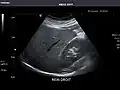

Kidneys: Right and left kidneys measure 11.5 cm and 12 cm in length respectively. No hydronephrosis. Small left lower pole kidney cyst.

Right kidney -

Left kidney -